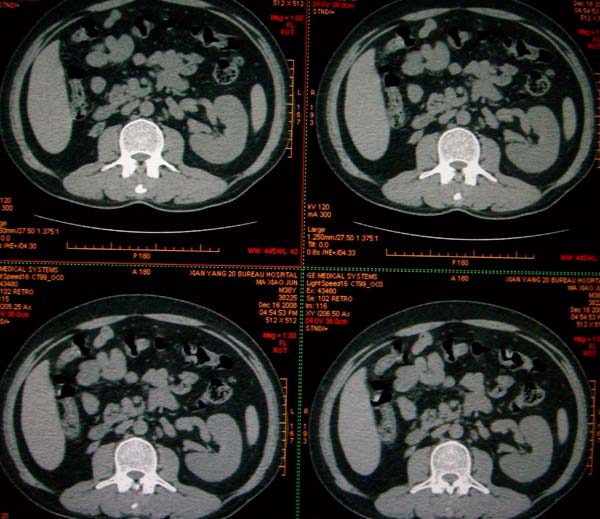

标题: CT17174:M38Y,体检超声提示右肾发育不良,病人无明显不适 [打印本页]

标题: CT17174:M38Y,体检超声提示右肾发育不良,病人无明显不适

右肾发育不良;考虑左肾下极血管平滑肌脂肪瘤可能,建议增强。

右肾微小发育不良  左肾下极错构可能

支持临床诊断,左肾改变需强化明确性质

1)左肾下极占位性病变,不排除肾癌可能;建议行进一步检查。2)右肾发育不良。

左肾下极占位性病变,不排除肾癌可能;建议增强及明确内部组织ct值。右肾发育不良。

右肾发育不良。左肾下极占位。

右肾发育不良。左肾代偿。左肾下极占位,性质待定,建议强化。

右肾发育不良

右肾发育不良。左肾下极占位。建议增强!

右肾发育不良。左肾下极占位。  强化

右肾发育不良。左肾下极囊实性占位,建议增强。